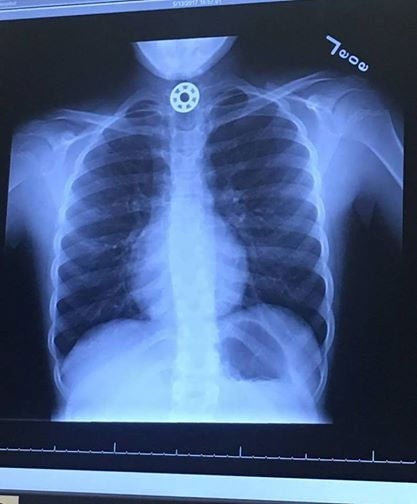

Letztendlich wurde das Leben der 10-Jährigen mittels einer Not-Operation gerettet. Wie das von der Mutter veröffentlichte Schock-Foto eines Röntgenbildes zeigt, steckte das nicht gerade kleine Metallteil bereits sehr tief in der Luftröhre, weshalb es nur mehr von Ärzten entfernt werden konnte. Während der OP durchlief die Frau bange Minuten. Glücklicherweise nahm die Geschichte ein gutes Ende. Mittlerweile können Mutter und Tochter schon wieder lachen: